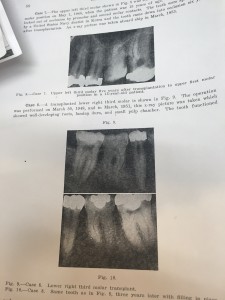

一番最初に、Fig1を見て下さい。移植にベストな歯です。って書いてあってですね、Fig1を見ると

こうゆう感じの歯がベストだそうです笑(Type Of Tooth Best Suited Transplantation)

こうゆう感じの歯がベストだそうです笑(Type Of Tooth Best Suited Transplantation)

なんか、もっと、移植に向いている何かをまとめた表みたいなのを期待していたのに・・・笑

まとめると

完全埋伏歯である。

根未完成である

傷つけない

乾燥させない

というのが大事だそうです。テクニックといいつつ、具体的な抜き方みたいなのは書いてありませんでした。